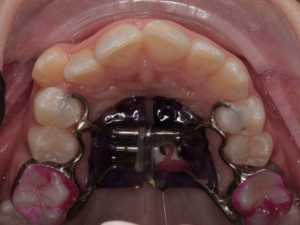

Классический аппарат состоит из винта хайрекс, пластмассового базиса, опорный колец на молочные моляры и направляющих к молочным к клыкам.

Но, конечно же, в зависимости от клинических ситуаций могут быть индивидуальные модификации. Например, при преждевременном удалении молочных зубов. В таких случаях опорные кольца изготавливаются на постоянные шестые зубы.

Аппарат Хааса один из немногих ортодонтических аппаратов , который позволяет достигнуть скелетного расширения в период активного роста ребёнка. Чем это обусловлено? Верхняя челюсть состоит из двух половин, которые связаны нёбным швом (хрящ). Именно он является зоной роста верхней челюсти. Воздействуя на эту зону : разрывая, растягивая её, стимулируется скелетное расширение. Но оно возможно до определённого возраста, пока шов не окостенеет. Поэтому данный ортодонтический аппарат используется в среднем от 5 до 12 лет.

Изготавливается аппарат Хааса только по индивидуальным оттиском ребёнка, чаще всего в 2 этапа:

- Снятие оттисков с обеих челюстей и подбор индивидуальных опорных колец

- Снятие оттиска с верхней челюсти, на которой установлены уже индивидуальные кольца

И уже по гипсовой модели с опорными кольцами изготавливается аппарат в лаборатории.

Ребёнок сам выбирает цвет и героя, который будет жить у него в полости рта.

Далее конструкция фиксируется в полости рта и врач проводит обучение родителей активации винта и даёт рекоммендации.

После установки врач-ортодонт обучает родителей активировать винт в полости рта ребёнка специальным ключом.

Активации чаще всего производятся 1-2 раза в день. Сроки активации в среднем 3-4 недели. За это время винт практически полностью раскручивается. Но помним, что это стандартый протокол лечения, могут быть индивидуальные корректировки в зависимости от конкретной ситуации в полости рта.

Далее винт «стабилизируется», т.е. заливается специальным материалом для того, чтобы после прекращения его раскручивания он стал неподвижным.

Аппарат Хааса состоит из колец на первые постоянные моляры или вторые молочные моляры и дополнительных лапок на молочные клыки или колец на первые премоляры, а так же имеет пластмассовый базис с винтом Hyrex, который плотно прилегает к слизистой оболочке неба.

Как подкручивать аппарат Хааса? - для этого есть специальный ключ, которым родители самостоятельно активируют аппарат по схеме доктора.

Первая активация обычно самая сложная для родителей, поэтому я напишу несколько рекомендация по активации аппарата:

1. Посадите ребенка или можно положить на кровать

2. Настройте освещение — можно фонарик или настольную лампу, чтобы хорошо увидеть аппарат и место постановки ключа.

3. Необходимо найти винт и паз — дырочку, которая находится ближе к вам.

4. Вставьте туда ключ, проверьте, что он хорошо там фиксируется

5. Придерживая пластмассовый базис аппарата пальцами второй руки, прокрутите ключ до упора в сторону неба

6. При полной активации вы должны увидеть новый паз

7. Аккуратно достаньте ключ в направлении неба. В этот момент главное - не скрутить винт обратно. Это может произойти, если вы не достали ключ из паза и начали вынимать из полости рта.

Чаще всего аппарат Хааса применяется в детской ортодонтии. Именно в данном возрасте мы можем влиять на рост челюстей, тем самым создавая место для постоянных зубов и корректируя прикус. Дети могут самостоятельно выбрать любимый цвет и картинку для аппарата. Результаты лечения более стабильны и прогнозируемы. Однако аппарат Хааса может применяться во взрослом возрасте. Так как костные структуры уже все сформированы, использование этого аппарата возможно только совместно с хирургически-ассоциированным послаблением небного шва. Показания к применению такие же, как и в детском возрасте. В результате, пациент получит широкую красивую улыбку.